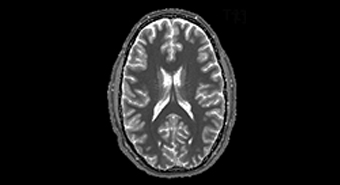

Die MR Gruppe beschäftigt sich in erster Linie mit der Entwicklung von neuen Methoden auf dem Gebiet der Magnetresonanztomographie (MRT) und den hierzu benötigten Messsequenzen. Der Schwerpunkt unserer Forschung liegt in der Hirnforschung. Insbesondere interessieren uns die Quantifizierung der MR Daten, die strukturelle und funktionelle Bildgebung, Bildgebung von Natrium sowie der Bereich der Hochfeld MR.

- Quantitative Bildgebung

- Neuartige Kontrastmechanismen